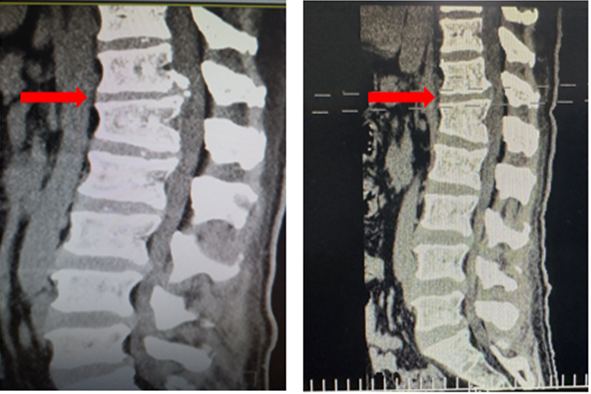

,均建议采取传统外科开放手术治疗,患者因担心手术风险,迟迟不愿手术。经多方打听,患者慕名找到李全义主任医师,李全义主任医师接诊后,仔细研究患者的疾病特点,腰椎间盘突出症常见于低位椎间盘(L4/5、L5/S1),而该患者属于高位椎间盘突出(胸12/腰1节段),并且已经引起了马尾综合征,表现为会阴部及鞍区疼痛、麻木、二便障碍,高位椎间盘突出因高位椎管不如低位椎管容积大,在穿刺时容易损伤神经,造成严重并发症。与患者经过充分的沟通,决定采用目前骨科前沿技术-----机器人辅助微创手术。在病院主任刘时璋教授的带领下,李全义主任医师团队顺利为患者实施ORTHBOT脊柱机器人辅助椎间孔镜下胸12腰1髓核摘除、椎管扩大减压术,手术在局部麻醉下进行,以机器人辅助微创手术解除了患者的痛苦,减少手术创伤及并发症,缩短手术时间。

患者术前(左)及术后(右)影像学资料